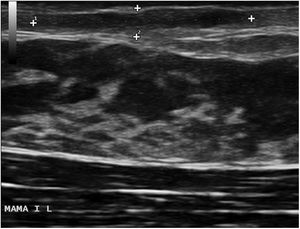

En la exploración clínica, se apreciaba un área indurada, eritematosa y elongada periareolar izquierda, dolorosa a la palpación (fig. 1). En la ecografía se visualizó en la dermis superficial una imagen longitudinal en banda hipoecogénica de 15×2,4×6mm, doppler negativa, compatible con un trayecto fistuloso (fig. 2). Con estos hallazgos la paciente fue diagnosticada de FM. Se pautó tratamiento con triamcinolona intralesional con lo que se consiguió la resolución clínica y ecográfica de la lesión. La paciente no presentó recidiva durante los siguientes 6 meses de seguimiento (fig. 3).